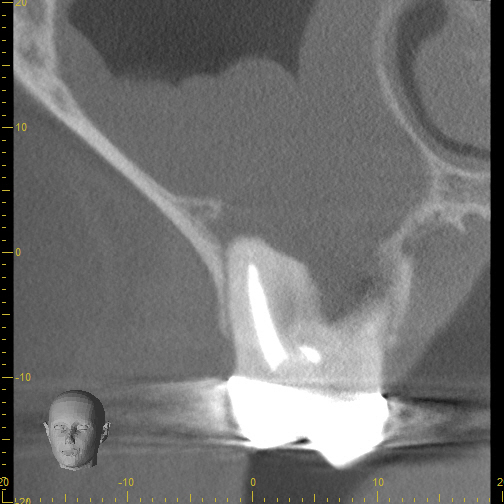

Case 5

Another case showing dramatic healing from root canal treatment. This patient had chronic sinus inflammation that never seemed to heal. The cause--an infected tooth. The top row images show both an erosion of the sinus floor from the tooth roots into the sinus cavity, as well as significant inflammation (swelling) of the sinus soft tissues that line the sinus. During retreatment I was able to find and clean all the canals, including one canal that was previously missed during the first root canal (I did not treat the original root canal). The bottom row images (one year later) shows complete re-establishment of the sinus floor (the bone that separates the sinus from the teeth) and complete resolution of the sinus swelling. There is no more infection. This retreatment case shows that even if a root canal treatment has failed, it can still often be saved. Always seek evaluation from an Endodontist before pulling out a "failing root canal"!